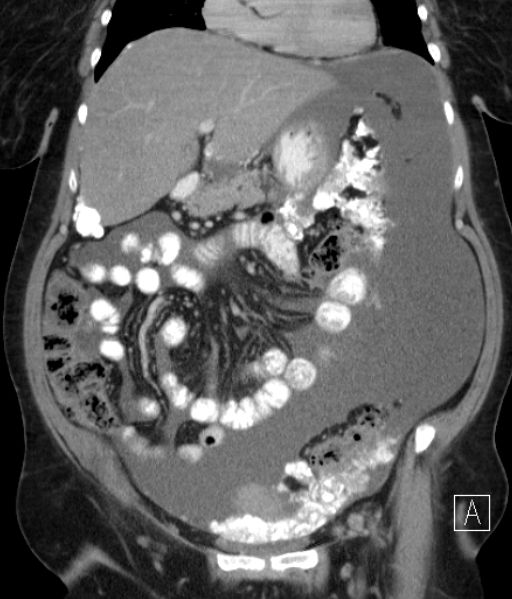

| Fall 2 | 58-jährige Frau mit Adnektektomie beiderseits vor vielen Jahren. Jetzt Peritonealkarzinose mit Verkalkungen. CA 12-5 = 1100, CA 15-3 = 41. Histologie: Proliferate und Infiltraten eines papillär strukturierten Karzinoms. Vergrößerte hyperchromatische Zellkerne. Die mitotische Aktivität ist etwas erhöht. Darstellung von Psammomkörpern. Tumorzellen positiv mit BerEP4, CK 7, WT1 und Östrogenmarker. Kein Nachweis von Calretinin und CK. | |||